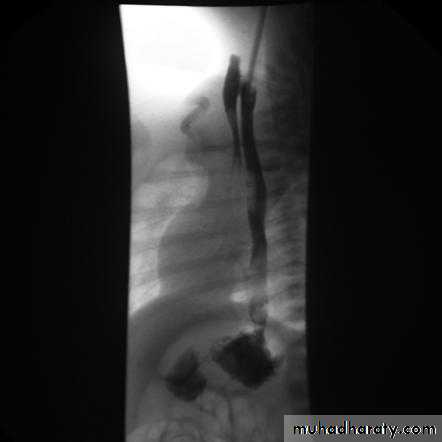

It is a neuromuscular abnormality result from failure of relaxation of the cardiac sphincter, which present at barium examination as a smooth , tapered narrowing always at the lower end of esophagus (bird beak or rat-tail appearance).There is associated dilatation of the esophagus, which often shows absent peristalsis. The dilated esophagus usually contains food residues and may be visible on CXR. The lungs may show consolidation and bronchiectasis from aspiration of the esophageal contents. The stomach gas bubble is usually absent.